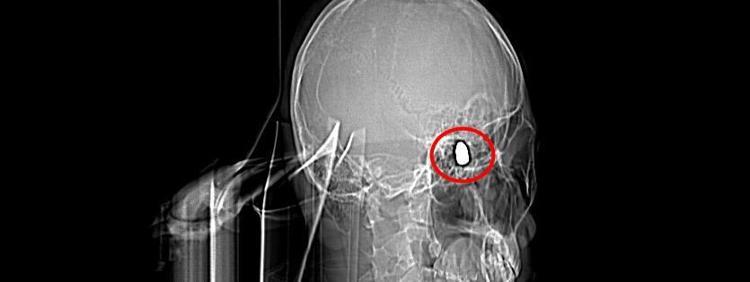

Olay, 5 Kasım 2023’te Bahçelievler Mahallesi 1624'üncü Sokak'ta meydana geldi. Arkadaşları ve ağabeyiyle maça gitmek için evinden çıkan Yusuf Emre Özbek, birlikte fotoğraf çektirdikten hemen sonra yere yığıldı. Çevredekilerin hastaneye götürdüğü Yusuf’un çekilen röntgeninde, başında mermi çekirdeği olduğu tespit edildi.

4 gün yoğun bakım, 4 gün de serviste tedavi gören Yusuf’un başındaki mermi için doktorlar, riskli bölgede olduğu gerekçesiyle müdahale etmedi. Düzenli olarak kontrol edilen Yusuf’ta konuşma güçlüğü ve sağ el ve parmaklarında zayıflık belirtileri ortaya çıkınca, fizik tedavi süreci başladı.